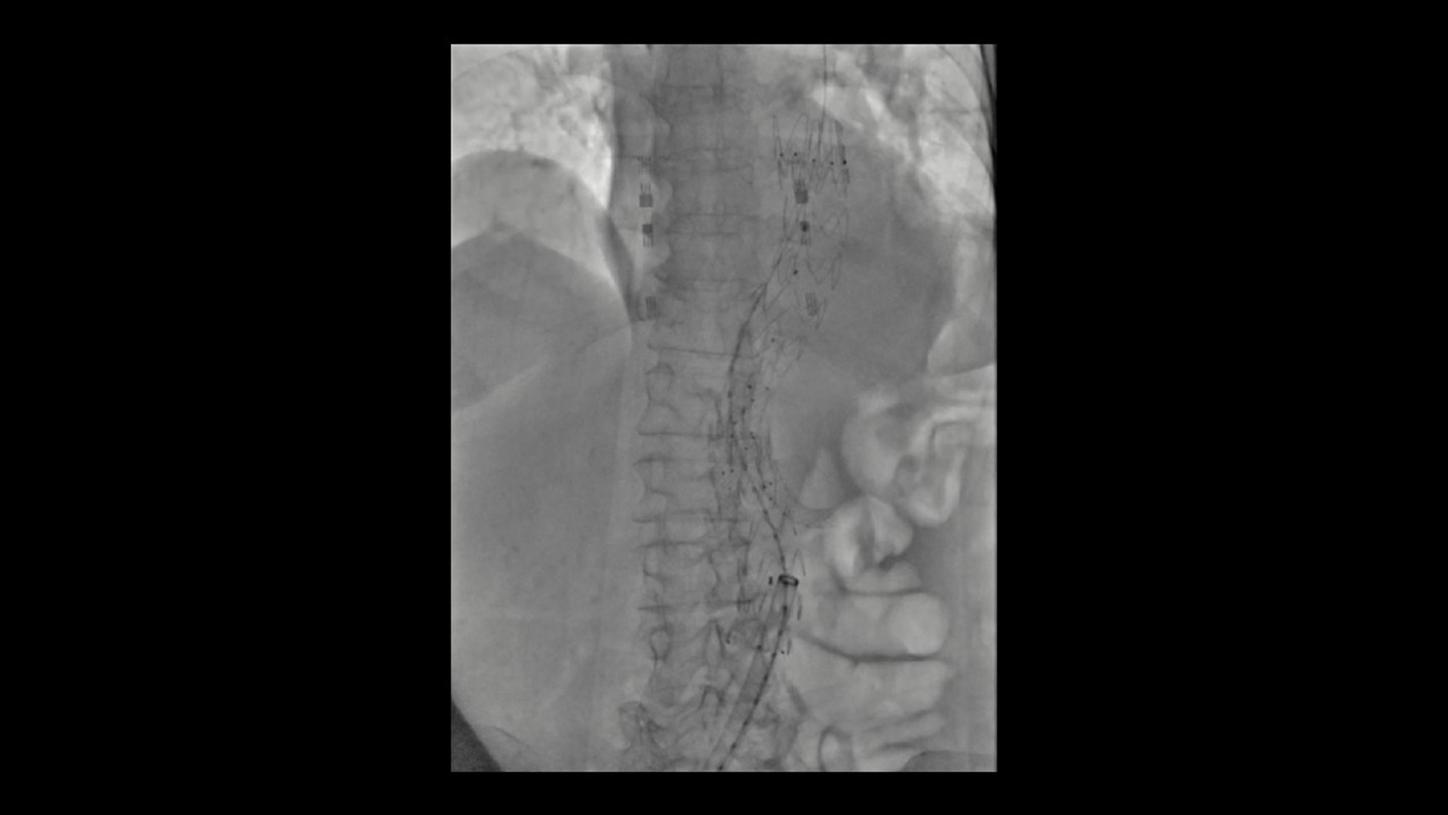

During minimally invasive procedures, it is critical to have a clear view of anatomies and devices. Yet complex imaging tasks or challenging patient conditions often impact image quality. OPTIQ AI delivers constant image quality1 defined by CNR in support of the ALARA principle, independent of patient or C-arm angulation. On top, an AI-powered algorithm reduces image noise in real time across different 2D imaging modes.

Make AI-powered imaging and clear insights your standard during interventions – with OPTIQ AI.

Future-focused IR imaging for a broad procedure mix

Discover how leading clinicians are transforming interventional radiology with Siemens Healthineers technologies. From ultra-fast 3D imaging to laser-guided needle procedures, the ARTIS icono ceiling powered by OPTIQ and syngo DynaCT are redefining what’s possible in IR. Explore real-world cases, expert insights, and the future of image-guided therapy.